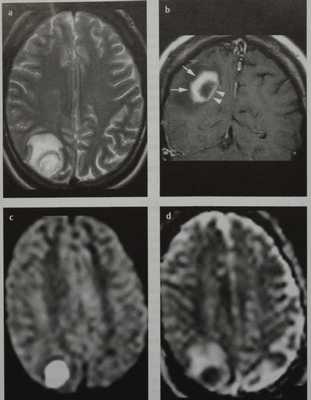

Абсцесс головного мозга. МРТ, Т2-ВИ в аксиальной плоскости (а), Т1 -ВИ во фронтальной плоскости после введения КС (Ь), диффузионно-взвешенные изображения в аксиальной плоскости (с) и карта ИКД (d).В правых теменной и затылочной долях визуализируется

3. DWI/ADC:

• высокий DWI-сигнал обычно в центре

• представляет истинную ограниченную диффузию (низкий сигнал на ADC, обычно -650+/-160 * 10^-6 mm^2/s)

• периферическая или неоднородная ограниченная диффузия; данная находка не является такой постоянной, поскольку около половины очагов с кольцевидным усилением могут не являться абсцессами

• значения ADC возрастают при успешном лечении

2. Т2/FLAIR:

• высокая интенсивность центральной области (гипоинтенсивна по отношению к ЦСЖ, не ослабляется на FLAIR)

• высокая интенсивность периферических областей (вазогенный отек)

• капсула абсцесса может выглядеть как тонкий обод низкой интенсивности

1. Т1:

• низкая интенсивность центральной области (гиперинтенсивна по отношению к ЦСЖ)

• низкая интенсивность периферических областей (вазогенный отек)

• кольцевидное усиление

• может быть вентрикулит